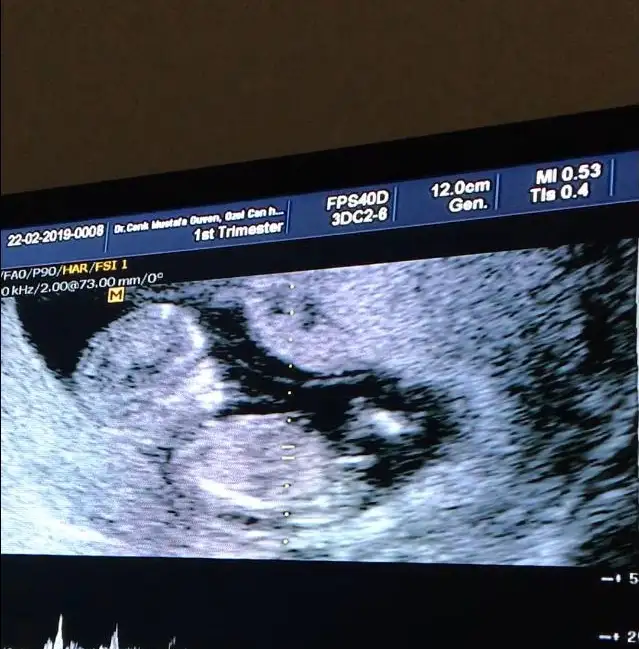

İkili için ölçümlerim güzel çıktı. Ense 1,25 çıktı. Çok iyi dedi doktorum. 3 ün üstü riskmiş. Burun kemiği var. Başka bişiler daha dedi hatırlamıyorum. Baş popo mesafesi günüyle uyumlu. Kan sonuçları 10 gün sonra çıkcak. Bizim kuzu uyuyordu rahat rahat ölçtü biçti doktor. Ama sonra dürttü göbeğimi ultrason cihazıyla. Zıplamaya başladı. Rahatsız oldu tipsiz :)

Cinsiyet sorduk. Kesin olmamakla beraber kız diyelim dedi ama o esas 16 da belli olur dedi. Zaten tam göremiyorlarsa genelde kız oluyor. Erkek tam gösteriyor o sebeple ben kız olarak bekliyorum valla :)

Videoya da çektim.

Bu da benim kızçem. Nub ( çıkıntı) bakmak isteyenler için :)